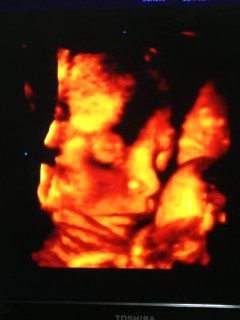

写真:32w1d:ケイトさん:こんなに開いたパー

なかなかお顔を見せてくれない息子ちゃん、今日のエコーでは手のひらを大きく開いてパーをして顔を隠していました(笑)先生もこんなに開いたパーをは珍しいね、と言ってくれました(^^)